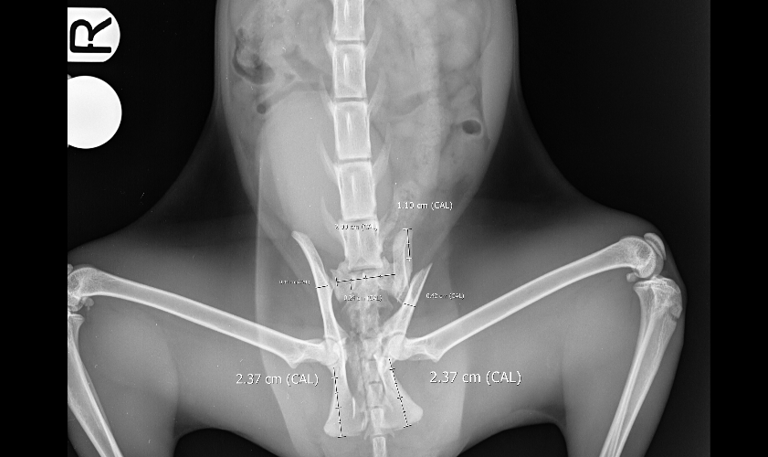

Case 4 - Luna

Cranial Cruciate Ligament Disease CCLD - American Bulldog, 5y, female